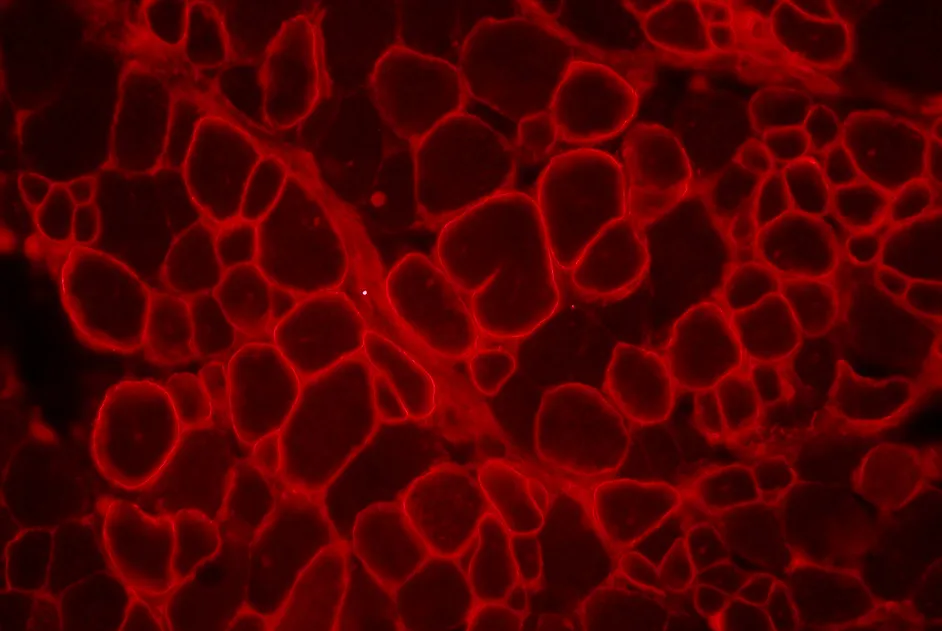

En 2010, une équipe américaine avait observé chez 2 patients atteints de dystrophie musculaire de Duchenne (DMD) sur 6 traités par une thérapie génique apportant le gène de la dystrophine, la présence d’une population de cellules immunitaires (lymphocytes T) qui reconnaissait des fragments de la dystrophine avant même que cette dernière n’ait été transférée.

Dans un article publié en juin 2013, cette même équipe a étudié la fréquence de cellules T dirigées contre la dystrophine chez 70 personnes atteintes de DMD (24 sous prednisone, 29 sous déflazacort et 17 sans traitement) et 21 personnes contrôles.

Les résultats de cette étude montrent que le risque de présence de cellules T anti-dystrophine préexistante à une thérapie génique augmente avec l’âge mais diminue avec les 2 traitements corticoïdes, suggérant que ceux-ci pourraient agir sur les réponses des cellules T anti-dystrophine. Toutefois, les patients sous déflazacort présentaient plus de cellules T anti-dystrophine que ceux sous prednisone.